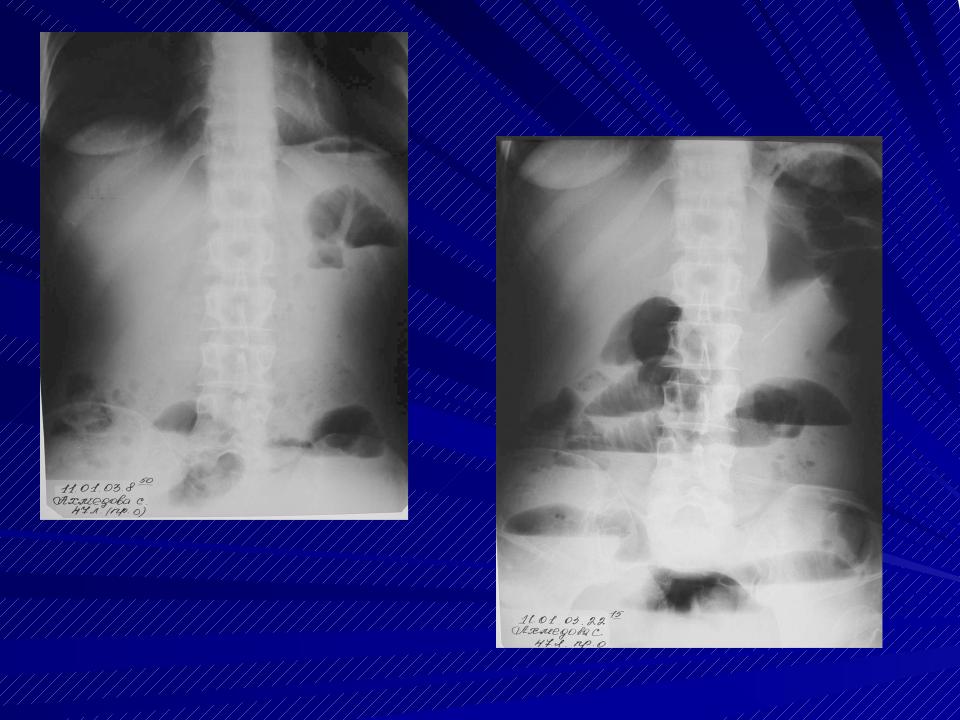

Иллюстрации и информация о симптомах острого кишечного непроходимости